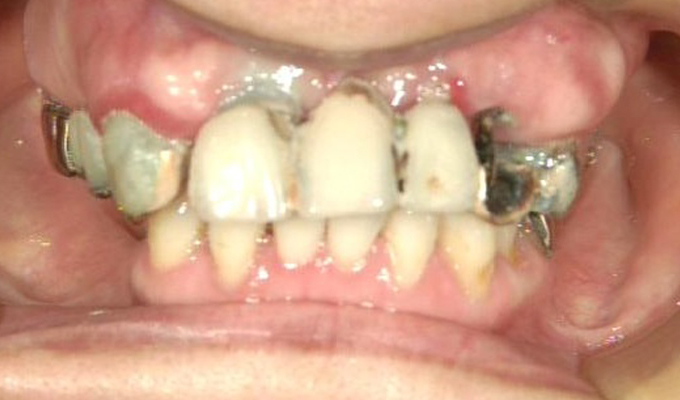

case1インプラントとメタルボンドブリッジの症例

最新メンテナンス時(2024年)

- 初診時の年齢

- 60代女性(2010年)

- 主訴

- ちゃんと咬めるようになりたい。最近孫が生まれたから一緒に歌ったりしたいけど、今は歌うこともできないから・・・・。と

- 治療内容

- 5年ほど前に入れ歯を作ったそうですが合わなかったので使用してなかったせいか前歯がグラグラになっていて今にも抜けそうな状態でした。

保存が難しい歯を抜歯し、上はインプラント8本、下は奥歯にインプラント4本埋入しました。

補綴は変色しないメタルボンドを選択されたので治療完了して11年経過してもとてもきれいな状態で維持されています。

初診時にお話しされていたお孫さんも中学2年生になったそうで、歯の治療をしたおかげで充実した毎日が送れてます、とメンテナンス時もいつも嬉しそうにされています。